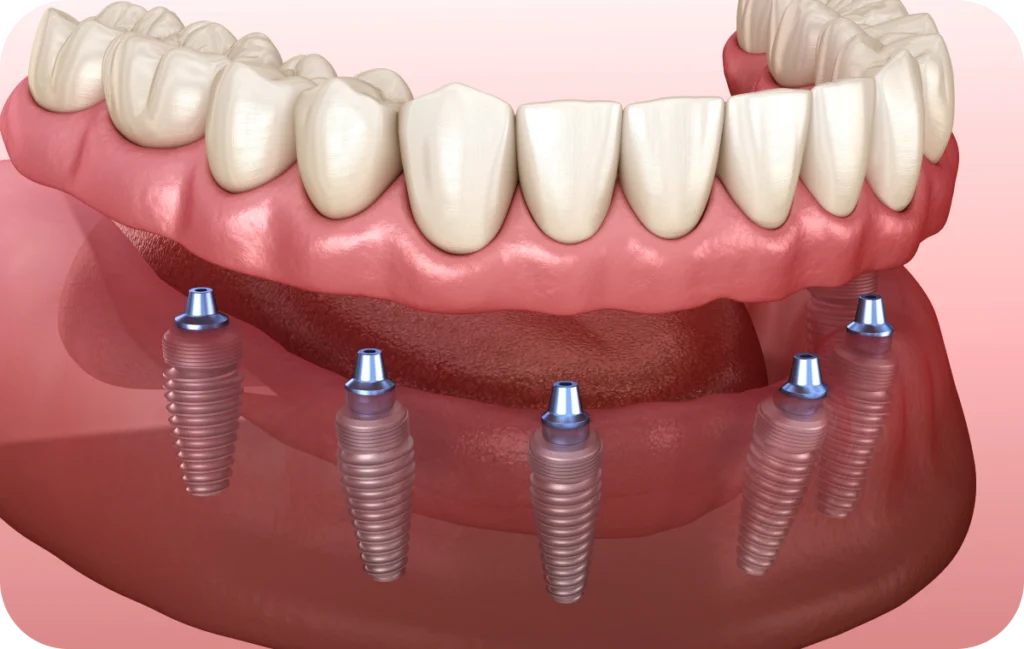

All on 4

Le protocole All-on-4 repose sur la pose de quatre implants par arcade. Deux implants sont positionnés verticalement à l’avant, tandis que les deux autres sont légèrement inclinés à l’arrière afin de maximiser la stabilité. Grâce à cette configuration, il devient possible de réhabiliter une arcade complète, même lorsque le volume osseux est limité. Ainsi, le patient bénéficie d’une solution fixe, durable et fonctionnelle, sans recourir à des greffes osseuses complexes.

All on 6

Le concept All-on-6 repose sur la pose de six implants stratégiquement répartis pour mieux absorber les forces de mastication. En augmentant le nombre de points d’ancrage, cette option offre une stabilité renforcée et réduit les contraintes mécaniques sur chaque implant.

Elle est particulièrement adaptée aux patients présentant une densité osseuse satisfaisante et souhaitant une solution à long terme à la fois robuste et esthétique. De plus, le protocole All-on-6 facilite souvent la répartition harmonieuse de la prothèse, améliorant le confort lors de la mastication.